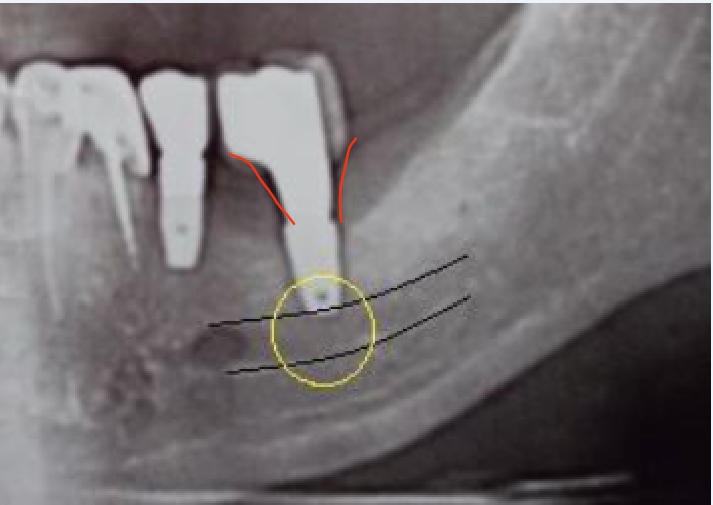

DoctorT Опубликовано 2 февраля, 2024 Поделиться Опубликовано 2 февраля, 2024 01.02.2024 в 08:36, Зндрю сказал: Три года назад слева снизу поставили два импланта : 4 и 6. Через 4 месяца на них установили две коронки. 4-ка работает лучше родного зуба, претензий нет. 6-ка под нагрузкой приводит к сильной боли , после снятия коронки боль уходит и в заглушенном состоянии имплант не тревожит. Проходил обследование на гальваноз и неврологию нижней ветви тройничного нерва - диагнозы не подтвердились . Другие имплантологи говорят, что боли в 6-ке возникают из-за нарушения пропорции корневой и коронковой частей конструкции. Установивший имплант хирург отрицает возможность переимплантации данной конструкции, объясняя, что кость слева снизу слишком тонкая и предлагает просто поставить заглушку на этот имплант и оставить всё как есть . Меня такой расклад не устраивает, хотелось бы на этом месте иметь полноценные жующие зубы со 100-% контактом с верхними зубами ( сверху напротив установлен цельнолитой мост ). Прошу совета, как мне быть - настаивать на удалении одного (или обоих) имплантов с последующей подложкой кости и переимлантацией, либо возможно проблемный имплант закрыть заглушкой и смоделировать другую конструкцию без удаления винтов и подложки кости ? Спасибо за ответы по существу. Если черным нарисован нижнечелюстной канал, то это не он, канал значительно ниже. Мне кажется, нужно поменять профиль прорезывания (придесневую часть коронки) и все должно пройти. Ссылка на комментарий

DoctorT Опубликовано 2 февраля, 2024 Поделиться Опубликовано 2 февраля, 2024 (изменено) Скорее канал так идет, если сделаете КТ то там точно видно будет. Изменено 2 февраля, 2024 пользователем DoctorT Ссылка на комментарий

Зндрю Опубликовано 2 февраля, 2024 Автор Поделиться Опубликовано 2 февраля, 2024 (изменено) КТ имеется . Окончание импланта лежит на нижней ветви тройничного нерва, но не травмирует его. Со слов независимого имплантолога, у которого был на консультации, иначе симптомы были бы неврологические , а их нет . Изменено 2 февраля, 2024 пользователем Зндрю Ссылка на комментарий

kramer Опубликовано 7 февраля, 2024 Поделиться Опубликовано 7 февраля, 2024 В принципе понятно. Лично мое мнение, что надо удалять оба имплантата (ближний выглядит недозаглубоенным (плохо видно), дальний слишком близко к нерву, что скорее всего и дает симптомы. Установить новые импланты, сделать мостовидную конструкцию. Ссылка на комментарий